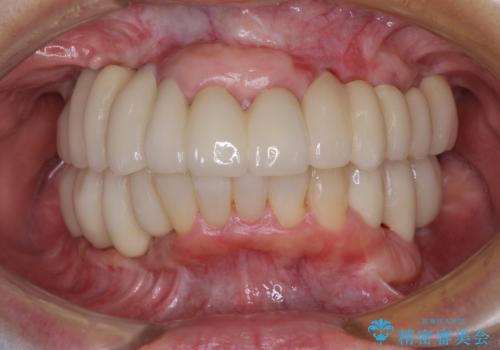

総合歯科治療 → インプラント&根管治療&矯正歯科